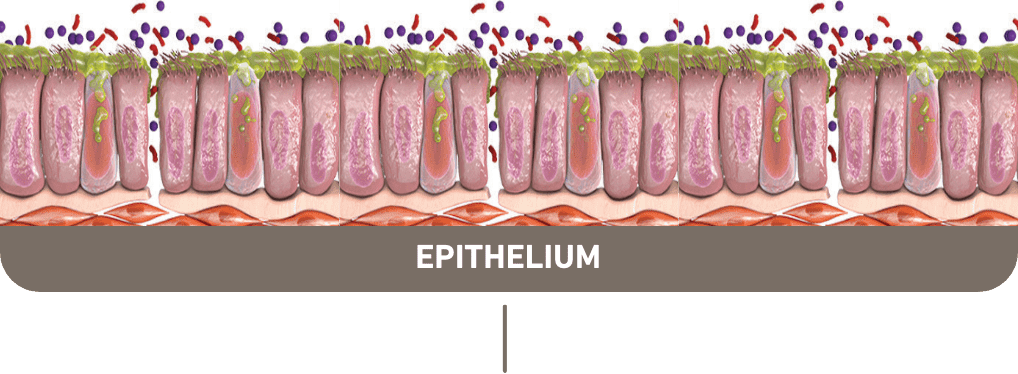

Up to 40% of COPD patients present with type 2 inflammation1-5,a

Multiple manifestations of

type 2 inflammation can

be seen in COPD

Mucus hypersecretion

Airway remodeling

and fibrosis7,8

Epithelial barrier

disruption8

Increased

FeNO8,b

Eosinophil

trafficking to the

lung tissues9,10

Parenchymal destruction11